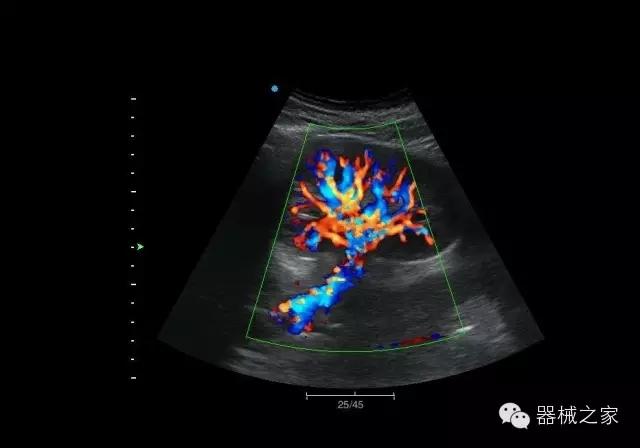

臨床圖片賞析

結(jié)甲

腎臟血流

肝血管瘤